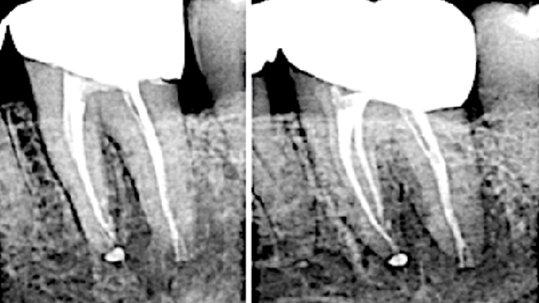

The multi-phase heat-treated file: Safeguarding against breakage of endodontic rotary files

Endodontic engine-driven (rotary files) have revolutionized modern root canal therapy by providing increased efficiency and precision. Despite these advancements, file breakage continues to pose a significant challenge, complicating treatment and potentially jeopardizing patient outcomes. To mitigate the risks associated with file separation, various methods and technologies have been introduced. This article explores the heat-treatment manufacturing … Read more